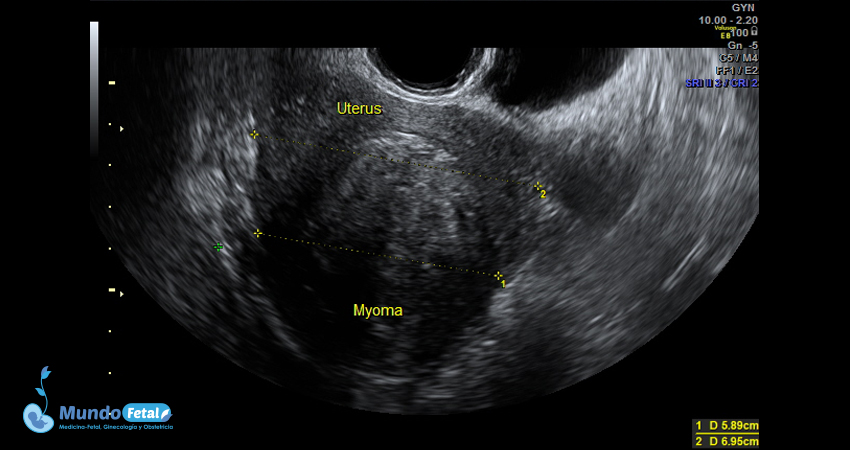

Ultrasonido Pélvico

Estudio anatómico de la región pélvica, que brinda información precisa de (vagina, cérvix, útero, endometrio, trompas de Falopio, ovarios y sus tejidos anexos) de cada uno, descartando alguna complicación de estas estructuras.